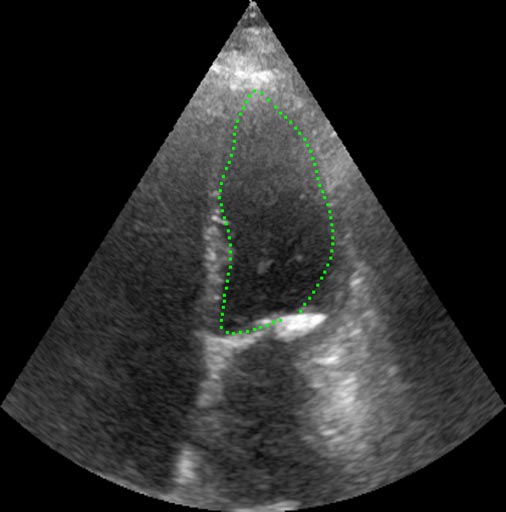

The result is a path with minimal cost, representing three-dimensional coordinates of a fluorescent tag particle throughout the image sequence. Tracking objects in a sequence of images is one of RSIP Vision’s fields of expertise. We have been utilizing dynamic programming and graph theoretic approaches to track not only tags, but also full organs, like in this heart monitoring system project.

Microscopy